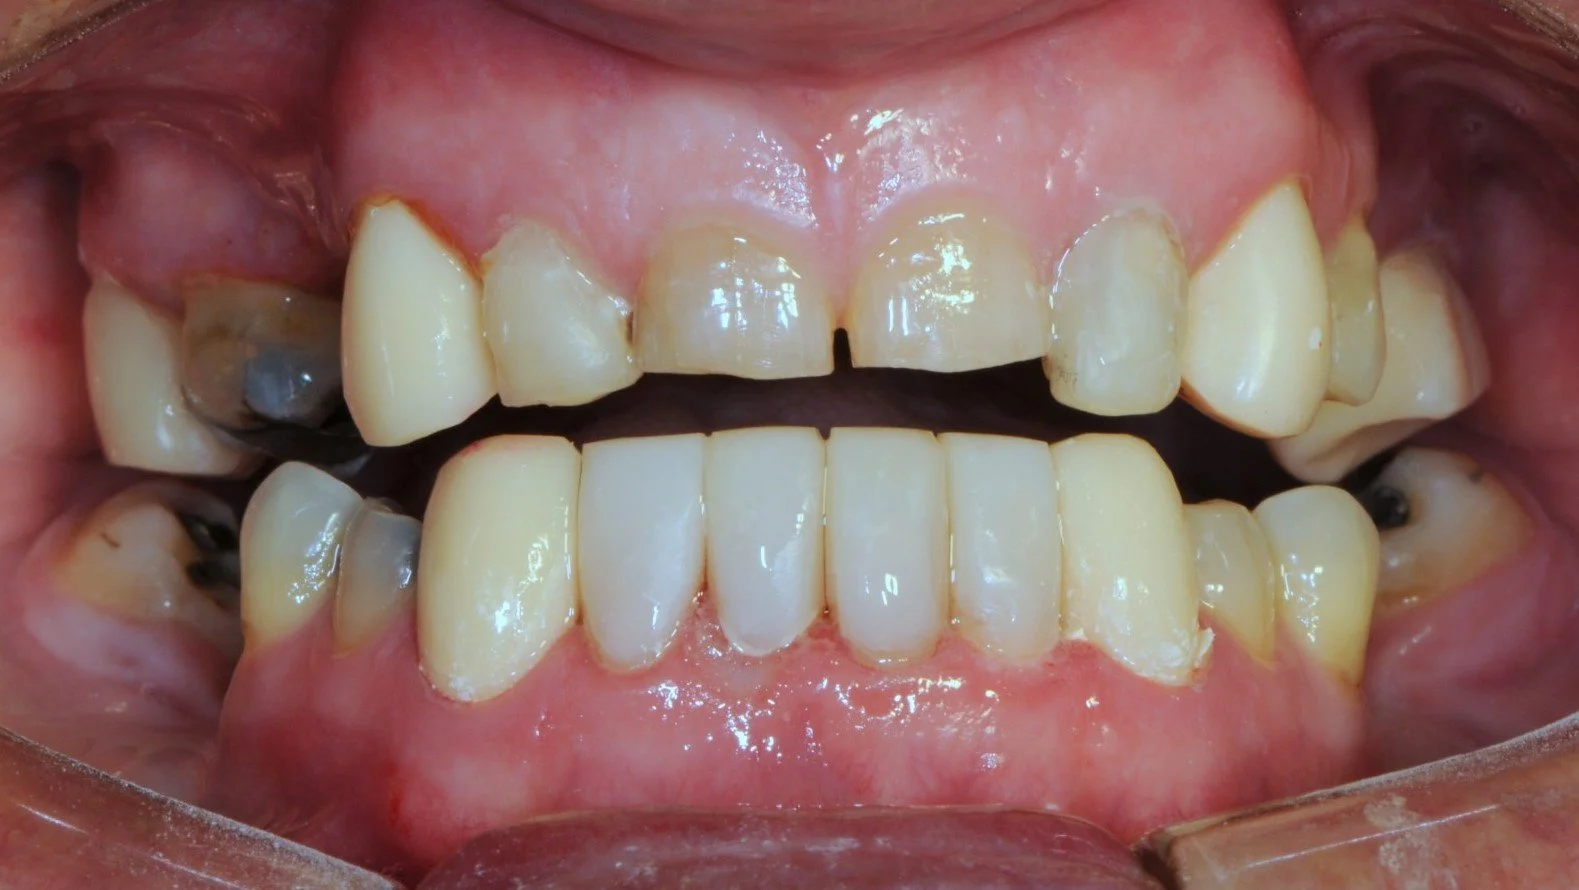

This 50 year old gentleman suffered severe dental wear, and heavily filled and stained teeth.

-

He endured a fractured lower jaw from a car accident resulting in the loss of the lower left canine with a residual space and a metal splint to fixate the broken jaw as is illustrated

Subsequently, the upper left front tooth fractured and was removed and I surgically placed a Branemark implant fixture/implant crown